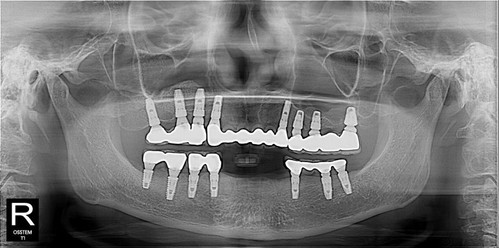

수술 중 불편할 기색을 비치셔서 걱정했지만

다음날 소독 받으러 오셔서는

"자면서 안 했으면 나 못했어. 자니까 수술 받았지"

이제 앞니 보철 할 때까지 기다리시기만하면 됩니다.~